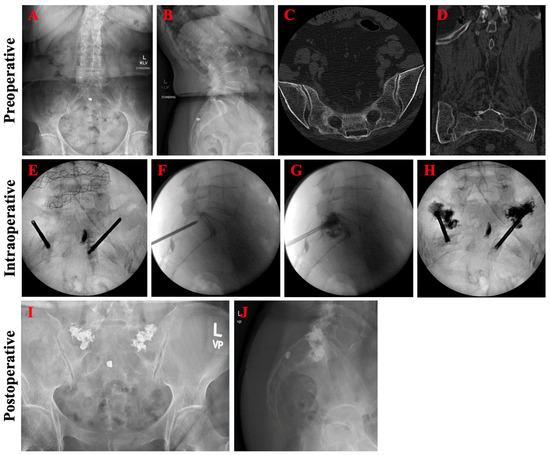

A 73-year-old female with a history of lumbar spinal stenosis presented with three weeks of lower back and bilateral hip/groin pain after falling off her bed and landing on her buttocks. Rest, ice, and over-the-counter pain medications had been ineffective thus far and she had become reliant on a cane for ambulation. Four-view lumbosacral spine radiographs demonstrated degenerative spondylolitic changes of the lumbar vertebrae (Figure 5A,B). Lumbosacral CT revealed bilateral Bakker B3 sacral fractures centered around S3 (Figure 5C,D). Bilateral sacroplasty through the bilateral short-axis approach was pursued without cement extravasation or other complications (Figure 5E–H). Post-operatively, pelvic radiographs showed adequate cement deposition at the fracture site (Figure 5I,J). Patient had marked improvement in pain (VAS from 8 to 5) and early return to ambulation independent of assistive devices.

Figure 5.

Pre-operative, intraoperative, and post-operative imaging for patient case 1. Pre-operative anteroposterior (A) and lateral (B) lumbosacral spine radiographs demonstrated degenerative spondylolitic changes of the lumbar vertebrae. Axial (C) and coronal (D) CT confirmed bilateral sacral fractures centered around S3. Intraoperative (E–H) imaging during bilateral short-view sacroplasty revealed adequate cement deposition at the fracture site. Post-operative anteroposterior (I) and lateral (J) lumbosacral spine radiographs showed good distribution of the cement without extravasation.